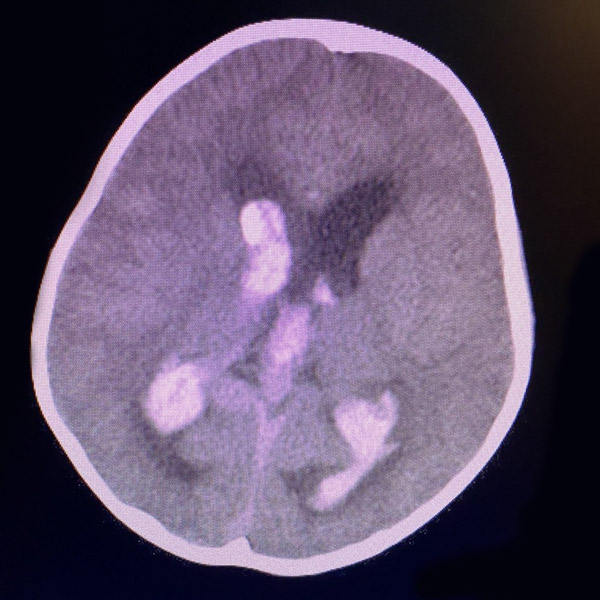

近日,一名7歲女性患兒因“突發意識障礙”,由外院急診轉至我院治療。通過急診CT檢查發現該患兒松果體區巨大占位并合并腦室血腫行成 ;急診腦血管造影明確為:大腦大靜脈球瘤。

我院迅速組織多學科MDT(神經外科、兒科ICU、放射介入科、麻醉科、手術室)討論制定詳細治療方案,征得家屬理解和簽字同意手術后,決定由神經外科血管介入組及顱底內鏡組進行聯合急診手術治療。神經介入醫師經股動脈置管行“彈簧圈+Onyx-18膠”致密栓塞靜脈球瘤控制出血,同時在高清神經內鏡輔助下行“腦室內鑄型血腫清除術”。